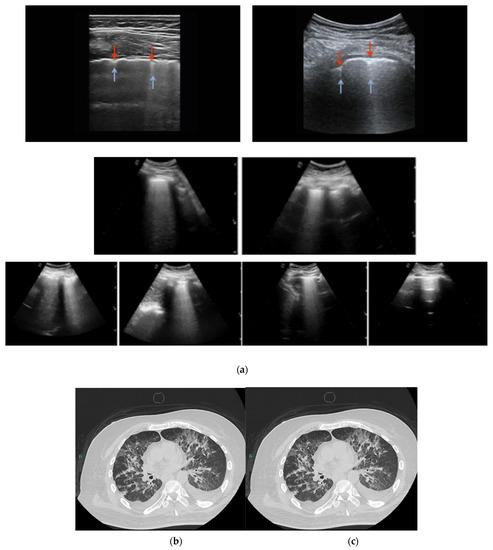

2.5. LUS Protocol

Lung Ultrasound Scoring System